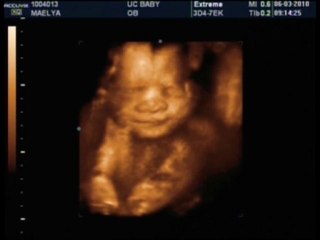

Echographie Souvenir 3D 4D chez Baby Live Montpellier